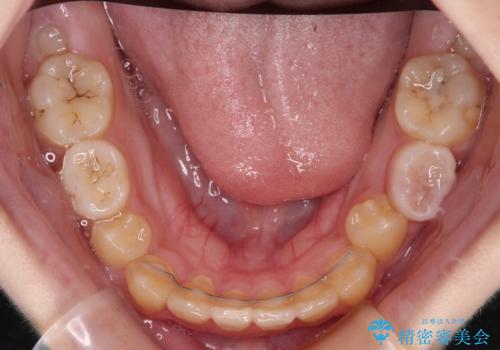

- 前歯の叢生を気にして来院された、小学校3年生女児の患者様です。

身長がやや低く、乳歯から永久歯への交換が少し遅い印象があったので、ワイヤー装置による1期矯正治療ではなく、乳歯も積極的に動かすことのできるインビザライン・ファーストにて治療を行うこととしました。

上顎前歯に過剰歯があったため、まずはその歯を抜歯し、傷が治癒したタイミングでインビザラインを発注することとしました。

インビザライン・ファーストは1.5年から2年程度の治療期間という制約がありますが、成人矯正(2期治療)をスムーズに行うための下準備期間として位置づけられており、2期治療を比較的安価かつ短期間で行うことができるようになります。